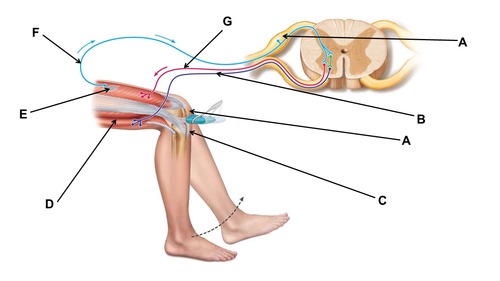

Name the region within bracket D.

This test could be used to test the functioning of which peripheral nerve?

femoral

When conducting this reflex, which muscle(s) are inhibited?

hamstrings

When conducting this reflex, which muscle(s) contracts?

quadriceps